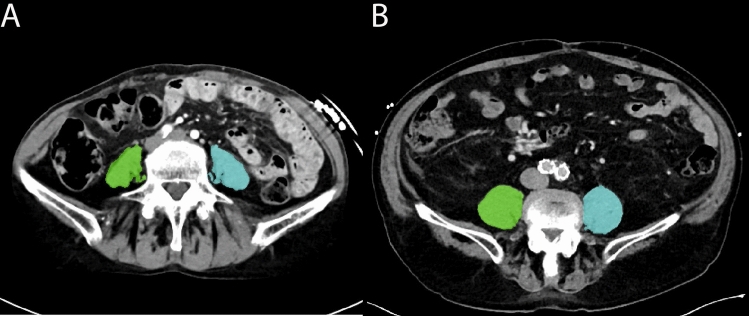

Transcatheter tricuspid valve repair (TTVR) might be an alternative option to reduce tricuspid regurgitation (TR) in patients with sarcopenia. Psoas muscle area (PMA) measured using computed tomography (CT) is known as a marker of sarcopenia. We investigated the association of PMA with procedural and clinical outcomes following TTVR. We retrospectively measured left and right PMA using pre-procedural CT in patients undergoing TTVR. Low PMA was defined as the total PMA < 20.3 cm2 for men and < 11.8 cm2 for women. The primary outcome was a composite of all-cause mortality and heart failure hospitalization within one year after TTVR. Of 163 patients, 47 (29%) were considered as having low PMA. Procedural success, defined as residual TR of ≤ 2 + at discharge, and in-hospital mortality were comparable between patients with low and high PMA. Patients with low PMA had a higher incidence of the composite outcome than those with high PMA (49% vs. 21%; p = 0.001) This association was consistent after adjusting for baseline characteristics (adjusted hazard ratio 0.43; 95% confidence interval: 0.23-0.80; p = 0.008). In contrast, the New York Heart Association functional class improved from baseline to three-month follow-up, regardless of PMA. Approximately 30% of patients undergoing TTVR were found to have low PMA. Although TTVR may be a safe therapeutic option to reduce TR and improve heart failure symptoms in patients with sarcopenia, the prognosis after TTVR remains poor in this population. Pre-procedural CT-based assessment of PMA may enhance risk stratification and support better clinical decision-making for TTVR.